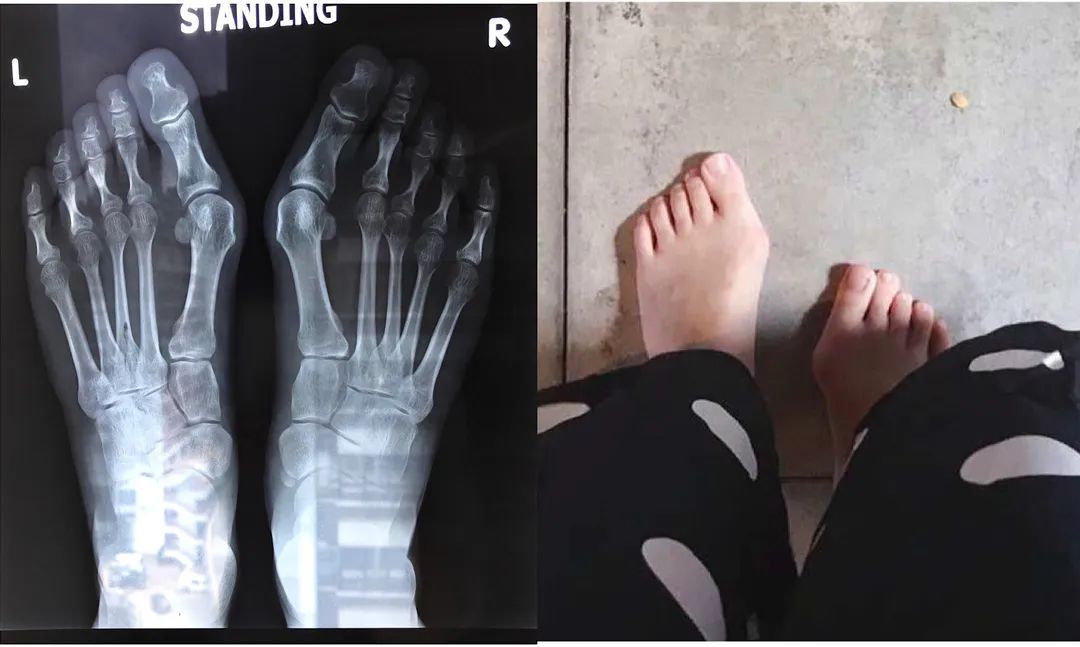

一、什么是拇趾外翻? 拇外翻(Halluxvalgus):也称大脚骨或第一跖趾关节炎,是指拇趾向外偏斜超过正常生理角度的一种足部畸形,是目前最常见的足病之一。女性发病多于男性,男女比例约1:91:15。 二、拇趾外翻的原因: 1、家族遗传因素占70%(母系遗传占比例较高)。日本人必买居家常备药4选:鸡眼、粗厚角质、拇趾外翻贴布超好用 日本自由行最常买的就是药妆了。 要知道哪些日本药妆最好用,当然要问日本人! 下面就为大家推荐日本家家户户都有的:「横山制药」4款热门常备药,从鸡眼、到粗厚角质、恼人小肉芽等 足小趾内翻畸形的治疗策略 郑永智 河南省中医院 小趾内翻又称小趾囊炎(tailor's bunion),主要表现为小趾的内翻和 (/或)第5跖骨的外翻,患足常有第5跖趾关节外侧的隆突,并伴有局部的红肿疼痛,以及第5跖骨头下的胼胝形成。 小趾滑囊炎 A,跖骨头增大 B